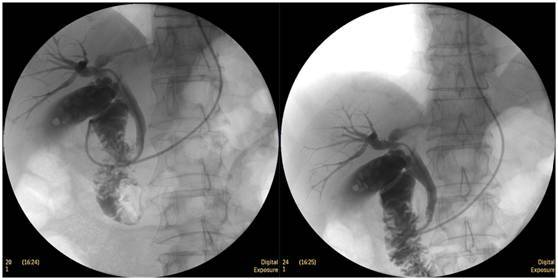

膽囊結(jié)石

ERCP膽囊顯影,見多枚結(jié)石影。

鼻膽管造影

立位注入造影劑,膽總管顯影好,稍擴(kuò)張,未見結(jié)石影。

膽總管結(jié)石

柱狀球囊擴(kuò)張完全,膽總管擴(kuò)張,下段見充盈缺損影。

膽總管擴(kuò)張,下段見明顯充盈缺損(上圖為反片且局部放大后效果)

柱狀球囊擴(kuò)張膽總管下段及乳頭(上圖為使用取石網(wǎng)籃取石)。